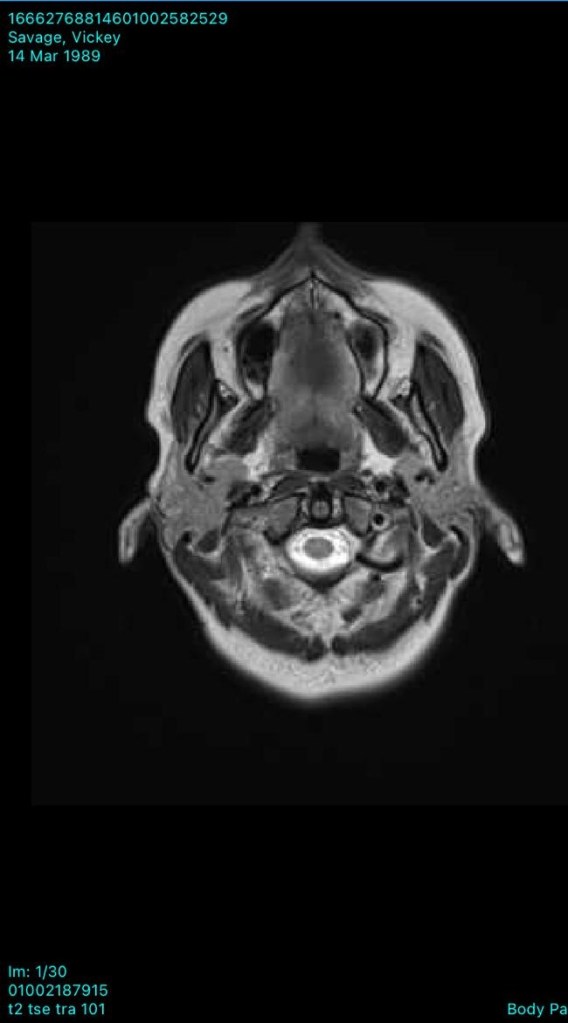

In December 2022, we later found out that there was a 13 mm cystic lesion on her pineal gland, in the limbic area of the brain, left sided. Below you will see her MRI scans from showing the cyst.

The pineal cyst in her mid brain has decreased in size, which they are also blown away by. The cyst was causing irritation to brain tissue and nerves. All physiologically induced via constant mobilisation of stressors! Through bringing down her sympathetic levels, signalling the Vagus Nerve, and inducing anti inflammatory and anti aging responses, this has been the outcome.